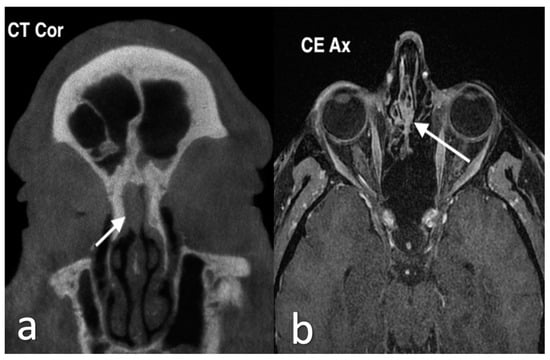

3.2.1. Lobular Capillary Hemangioma

3.2.2. Chondromesenchymal Hamartoma